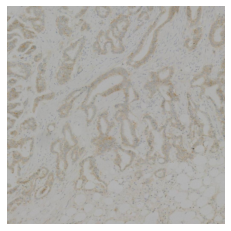

2.2 Embedding Knowledge from Additional Brightfield Images

To demonstrate the generality of the method, we train models on the BCI dataset [4] of paired H&E and brightfield IHC patches. We only perform evaluation on the BCI, NCT and PanNuke datasets, as the BCI dataset is a breast cancer dataset, while the Singapore and MHIST datasets are prostate and colorectal polyp specimens respectively, which are far out of the training distribution. We include the NCT dataset, despite comprising only colorectal tissue, as these patches are well curated into different tissue type classes which mostly bear a strong resemblance to those in breast cancer samples. Strikingly, TriDeNT ♆ outperforms the supervised baseline by a large margin on the BCI task. We propose that there may be features weakly present in H&E stains which are highly predictive of HER2 status, and the pairing with IHC stains which contain those features very strongly results in this improved performance.

As Table 1 shows, we find that TriDeNT ♆ is also highly effective on all tasks compared to the unprivileged Siamese baseline. As there is more information in the privileged paired data, the privileged baseline is considerably higher for this task. Despite this, TriDeNT ♆ still outperforms both comparable baselines on all tasks but one, achieving improvements of up to 25.1% compared to the unprivileged baseline and up to 5.8% compared to the privileged baseline. There is only a single task where TriDeNT ♆ does not improve performance: evaluation on the PanNuke dataset of a model trained with the VICReg loss, performing 1.6% less than the privileged baseline. The brightfield IHC stains contain considerably more task-relevant information for cell segmentation, so this is unsurprising. This effect can be understood visually as the IHC ‘weak’ quadrant in Figure 1(a) being very narrow and containing very few features. Most task-relevant features are strongly present in the IHC and therefore there is less to be gained by adding the few missing weak features.

Immunohistochemistry is an ancilliary staining technique often used in medical diagnosis, which works by using an antibody to target specific proteins in tissue. Secondary chemical processes are coupled to the antibody to produce a colour, making it much easier to identify their presence and location within tissue. There are many different antibodies used which each target a specific protein or protein type. Common examples of antibody targets include cytokeratins, which are found in epithelial cells, CD3, CD4, and CD20, which are found in various types of immune cells, and smooth muscle actin (SMA), which is found in myofibroblasts [55].

While H&E staining is the routine protocol for tissue analysis, pathologists usually rely on IHC or IF staining to obtain information about the locations of individual proteins, which may aid further investigation or confirm their diagnoses. IHC and IF stains therefore contain highly specific information about a particular protein, so add useful information beyond that which can be readily identified with H&E staining. While this is necessary for human pathologists to identify features which cannot be easily identified by eye in the generic H&E stains, for example separating the identities of individual epithelial, endothelial, myeloid cells and lymphocytes, it has been shown that neural networks can accurately reproduce many of these stains from only H&E [39]. It would be tempting to conclude, then, that this is a solved problem, and researchers should simply use these models to produce representations of H&E patches which contain features relevant to IHC or IF stains. Unfortunately, this has been shown to perform poorly [19], as image to image translation models are restricted to learning very fine grained information, such as the exact locations of nuclei, at the expense of the types of low-redundancy coarse grained features which are learned by self-supervised Siamese networks.

Nevertheless, the results of these works imply that much or all of the useful information in IHC and IF stains can be predicted from H&Es. We investigate how representation are affected by distilling information from IHC and IF stains into models of H&E stains, evaluating both brightfield IHC images and thresholded IF images.

S2.2 BCI: Breast Cancer Immunohistochemisty

Between 15-20% of breast cancers will overexpress the protein HER2 (Human Epidermal growth factor Receptor 2), which promotes the growth of cancer cells, and typically have worse prognosis than HER2-negative cancers [60]. Testing for HER2 is carried out using IHC staining, with 4 grades: 0, 1+, 2+, and 3+, with 0 being negative and 3+ being the highest positive grade. The BCI dataset [4] contains 4871 px patches from 51 H&E stained slices obtained from breast cancer patients, paired with corresponding spatially registered IHC patches. We split these into patches of size px for consistency with the evaluation datasets. We retained the same train/test split for the new patches, giving train/test datasets of size 62336/15632 respectively.

We primarily used BCI as a pretraining dataset to demonstrate the efficacy of TriDeNT ♆ for raw IHC paired with H&E patches, however, we also evaluated the pretrained model based on 4-class classification of HER2 status. The dataset was highly imbalanced (0: 5.18%, 1+: 23.59%, 2+: 43.56%, 3+: 27.67%) so we used proportional class weighting during classifier head training, but not self-supervised pretraining. For this reason we only used BCI as an evaluation set for the BCI pretrained models.